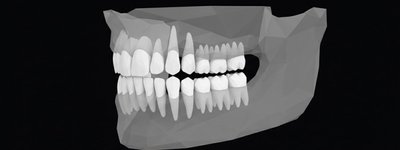

X-Ray of Baby Teeth: What It Shows, When It’s Needed, and Safety Tips

2/11/2026